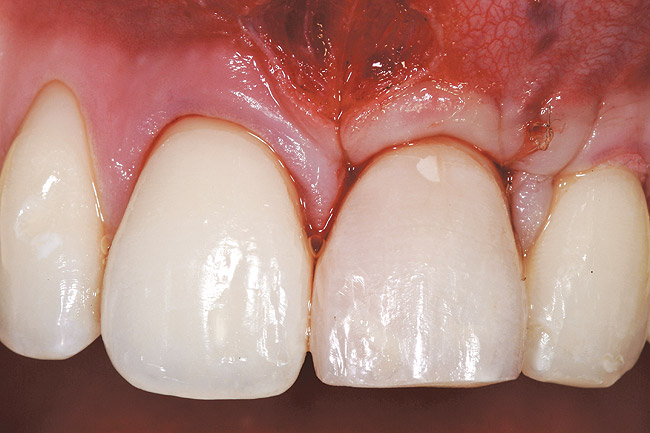

A 54-year-old non-smoking woman presented for correction of deep-wide gingival recession in the maxillary anterior (Figure 1 through Figure 3). The patient’s desires were to correct the gingival recession, balance the heights of contour of the tissues, and possibly undergo esthetic enhancement of the maxillary anterior with veneer restorations.

The 2.5-week postoperative clinical view can be seen in Figure 10 through Figure 12. Note the rapid soft tissue healing and maturation. At 6-weeks postoperative, tissue plasty was accomplished to blend the thickened keratinized tissue, in addition to placement of class V composite restorations at teeth Nos. 5, 6, and 11 to create a new restorative margin on the root surfaces.

The 2-month postoperative view can be seen in Figure 13 through 15. Note the color match of the tissue, balance of the facial heights of contour, and zones of attached keratinized tissue present.

Figure 10  Case One The 2.5-week postoperative view, maxillary anterior.

Figure 10

Figure 13  Case One The 2-month postoperative view, maxillary right.

Figure 13

Figure 14  Case One The 2-month postoperative view, maxillary anterior.